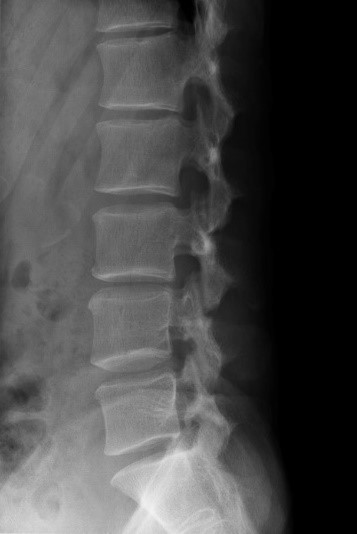

Дослідження ШКТ

Дослідження органів черевної порожнини, малого тазу